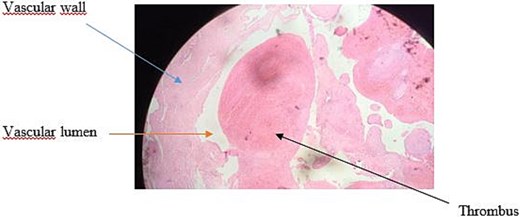

Histopathological examination revealed an aneurysmal arterial wall showing thrombotic changes with incipient fibrous organization (Fig. 4). After a clinical follow-up of 5 years, no recurrence of the aneurysm was detected.